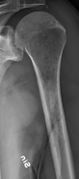

Femur with multiple myeloma lesions.

Humerus with multiple myeloma lesions.